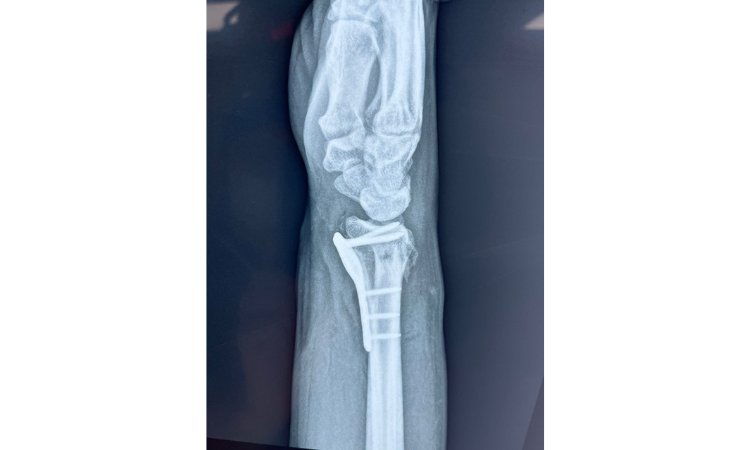

1. Radio: El radio es el hueso más grande del antebrazo y se encuentra en el lado lateral de la muñeca. Las fracturas del extremo distal del radio mas conocidas son las descritas como fractura de Colles o fractura de Smith segun la dirección del desplazamiento del fragmento. Estas fracturas pueden ocurrir debido a una caída sobre la mano extendida.

2. Cúbito: El cúbito es el otro hueso del antebrazo y se ubica en el lado medial de la muñeca. Las fracturas del cúbito pueden ocurrir en combinación con las fracturas del radio.

El diagnóstico se realiza mediante una evaluación clínica y radiografías. El tratamiento básico para las fracturas de muñeca implica la inmovilización adecuada del área afectada. Esto se logra generalmente mediante la colocación de un yeso o una férula para mantener los huesos en su lugar mientras sanan. En algunos casos, puede ser necesario realizar cirugía para realinear los fragmentos óseos.